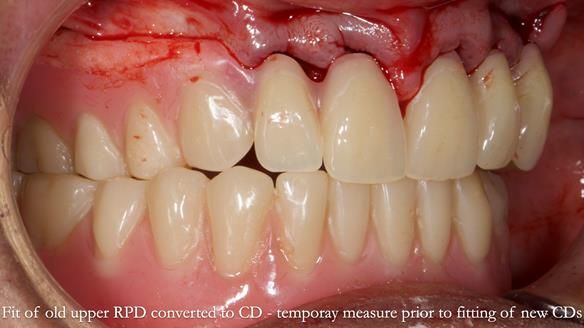

Welcome to Newsletter 62. In this edition, I walk through the process of removing 5 upper anterior teeth, adding to an existing upper RPD, followed by creating and fitting metal based complete dentures for Rafique, a 71 year old man.

The detailed clinical situation and treatment process are outlined below, with clinical work provided by me and technical work by Rowan Garstang. The treatment spanned 12 months, involving removing 5 upper anterior teeth, adding to an existing upper RPD, followed by creating and fitting metal based complete dentures.